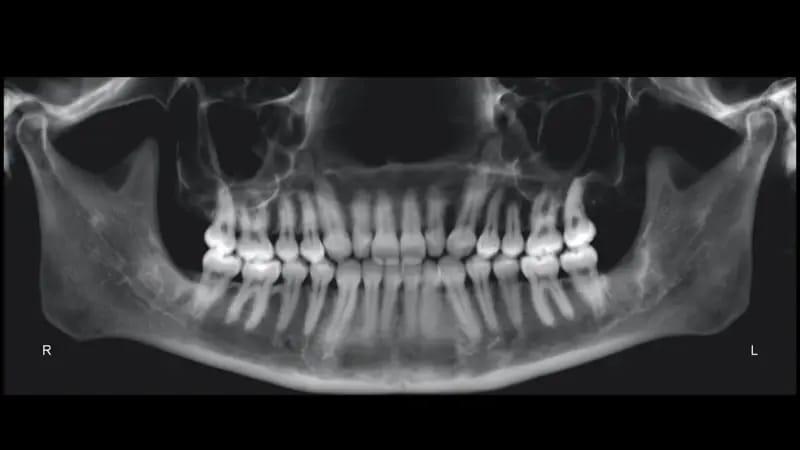

Панорамная рентгенограмма подтвердила наличие всех четырех зачатков третьих моляров. Примечательно, что в верхней челюсти наблюдалась выраженная резорбция корней, хотя общее состояние пародонта казалось хорошим (фото 3). Цефалометрический анализ показал тип скелета II класса, тенденцию к вертикальному росту и заднюю ротацию нижней челюсти. Было обнаружено, что резцы верхней и нижней челюсти слегка наклонены (фото 4).

Фото 3: Дооперационная панорамная рентгенограмма.